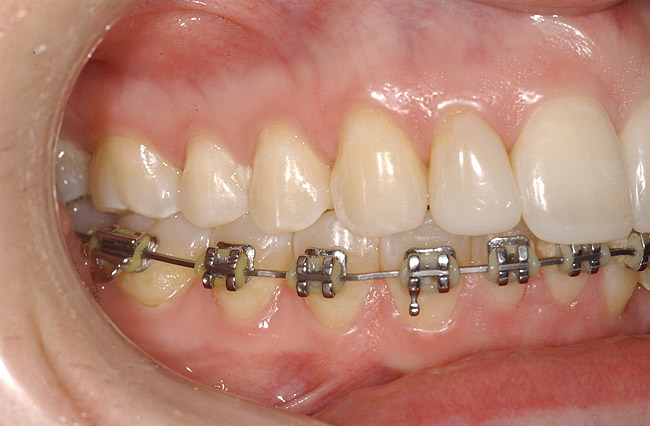

Figure 9: Orthodontic distraction osteogenesis to develop the implant site of tooth No. 23.

Figure 9

This treatment plan was elected with the premise to reevaluate treatment options during orthodontic tooth movement. Soft-tissue augmentation was initiated to correct the mucogingival defect in the area of teeth Nos. 21 and 22. A free gingival graft was performed to achieve an adequate band of attached and keratinized gingiva to resist potential stripping on the root surfaces of teeth Nos. 22 and 21 during orthodontic movement (Figure 8). Orthodontic movement then was initiated to site-develop position No. 23 for an implant (Figure 9 through Figure 11). Orthodontics also was used to idealize the patient’s occlusion and develop canine guidance to minimize occlusal load and maximize the redistribution of forces36-40 for protecting the future implant from deleterious forces. The space was opened around the peg lateral tooth No. 7, and the gingival levels were aligned for maxillary incisors. Bonding was performed to restore the length of teeth Nos. 8 through 10 and to bond the peg lateral to a normal tooth form, which allows the orthodontist to idealize the posterior occlusal scene and maintain canine guidance (Figure 12 through Figure 13).